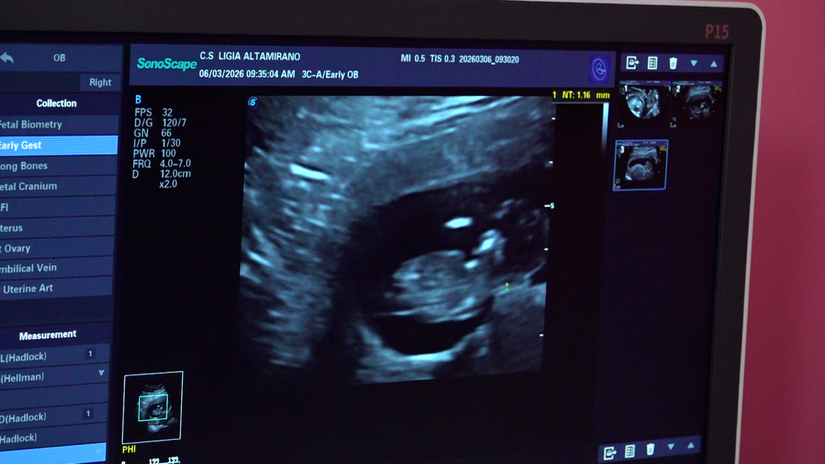

La doctora Judith García, directora del centro, comentó que a las mujeres se les realizan ecografías para evaluar la edad gestacional y el riesgo de presentar alguna anomalía congénita, preeclampsia o embarazo pretérmino.

“Estamos realizando estudios a mujeres entre las 11 y 13 semanas de embarazo, con una evaluación completa de su gestación, con un ultrasonido específico de tamizaje, en el cual se evalúan entre 100 y 150 embarazadas, provenientes de todo el departamento de Managua y del Silais-Managua”.